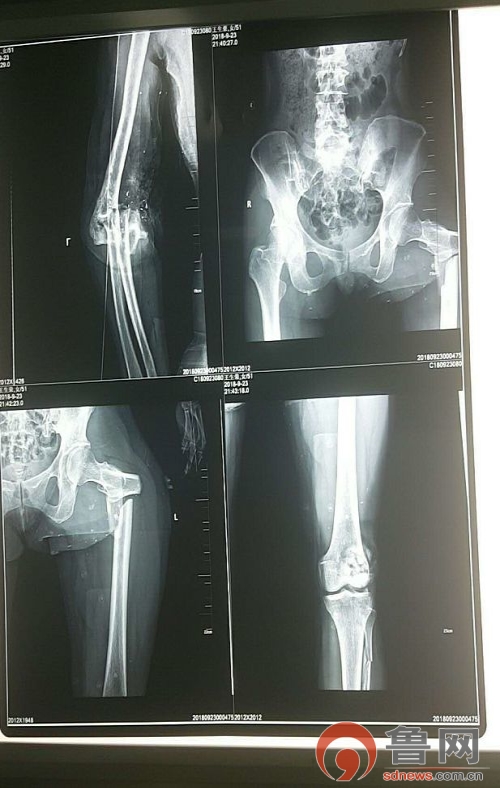

患者全身10余处骨折,面部外伤、双眼球破裂并异物滞留,失血性休克。病情危急,刻不容缓,补液,纠正循环,备血,输血,手足外科医疗团队成员先后赶到现场,讨论患者的救治方案,CT检查,排除胸腹部脏器损伤后紧急送入手术室。

患者足关节开放损伤、大面积皮肤软组织缺损、骨折脱位并骨缺损,髌骨开放性粉碎骨折并骨缺损,股骨近端粉碎性骨折,左足踝部多处骨折并脱位,患者创伤性休克,病情危急。团队经讨论决定,先对肘关节、膝关节两处开放性损伤进行手术,股骨近端、足踝部骨折二期手术的方案。

术中见髌骨粉碎严重,部分骨缺损,关节面严重压缩,左肘部开放性骨折、肘关节脱位、骨缺损伴严重污染。多根血管神经肌腱断裂,手术难度极大,为减少感染风险,避免增加手术创伤,术中给予彻底清创,仔细复位髌骨关节面及尺骨近端骨折以钛揽张力带内固定同时外固定架固定肘关节,救治医疗团队经过六小时的奋战,顺利完成了对肘关节膝关节严重开放骨折的手术。